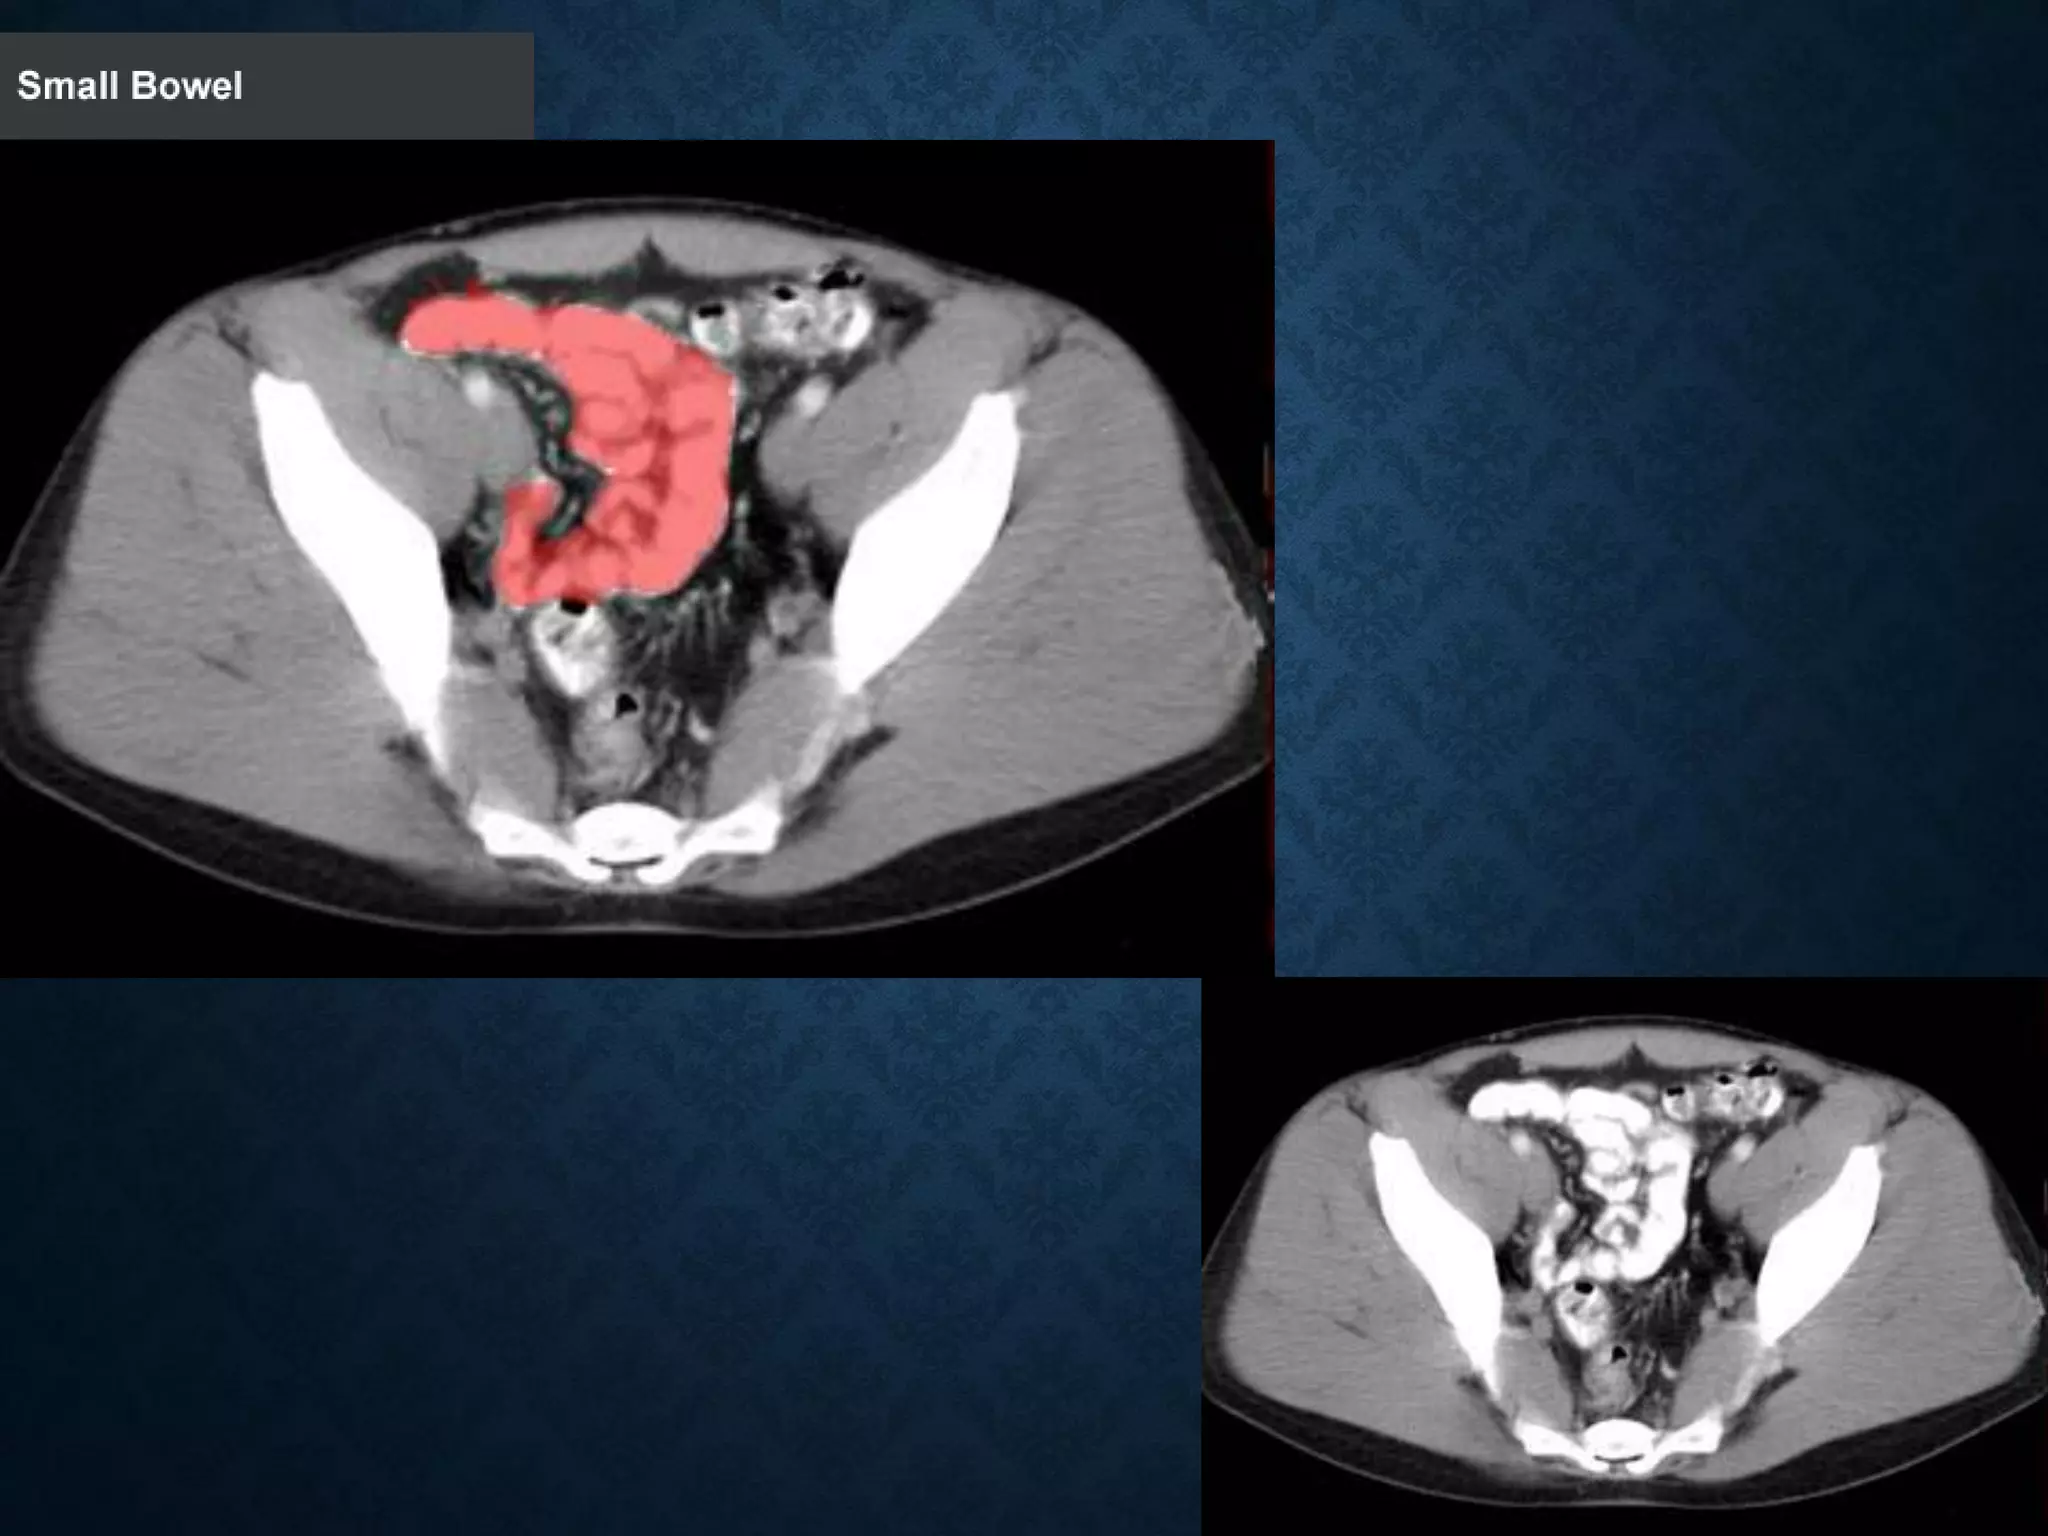

Identify the following structures in the body CT to the right. To view the location of the structure in the image click on

the label at the left and the structure will be indicated in the image. Abdominal CT scans typically begin just above

the diaphragm, so the first slice you see is of the lower chest.

Identify the followingstructures in the body CT to the right. To view the location of the structure in the image click on the label at the left and the structure will be indicated in the image. Abdominal CT scans typically begin just above the diaphragm, so the first slice you see is of the lower chest.